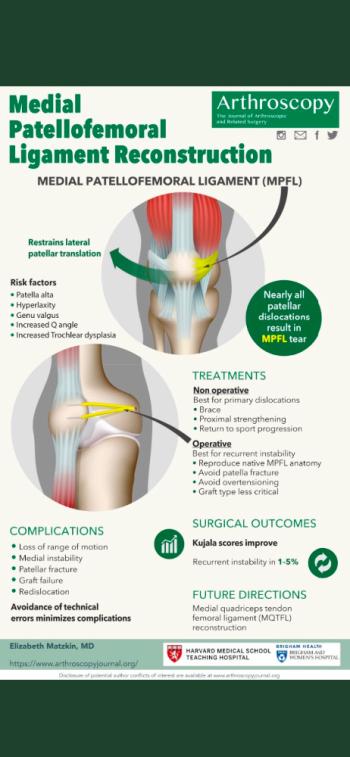

Patella (Diz kapağı) Çıkığı 9 OkunmaMPFL Rekonstrüksiyonu

Medial Patellofemoral Rekonstrüksiyon